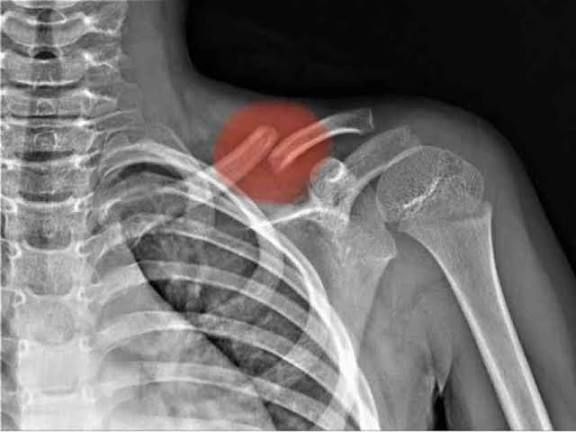

يبدأ التشخيص بفحص سريري يتبعه تصوير بالأشعة السينية لتحديد:

ـ مكان الكسر

ـ نوعه

ـ مدى انفصال الأجزاء

وفي الحالات المعقدة يستخدم الأطباء الأشعة المقطعية قبل وضع خطة العلاج.